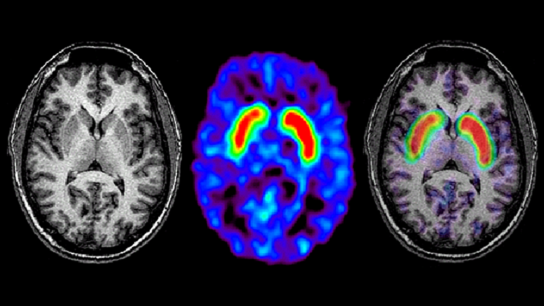

MRI may be used to identify Parkinson disease biomarkers that can inform diagnosis, track disease progression, and elucidate the neurobiological underpinnings of symptoms.